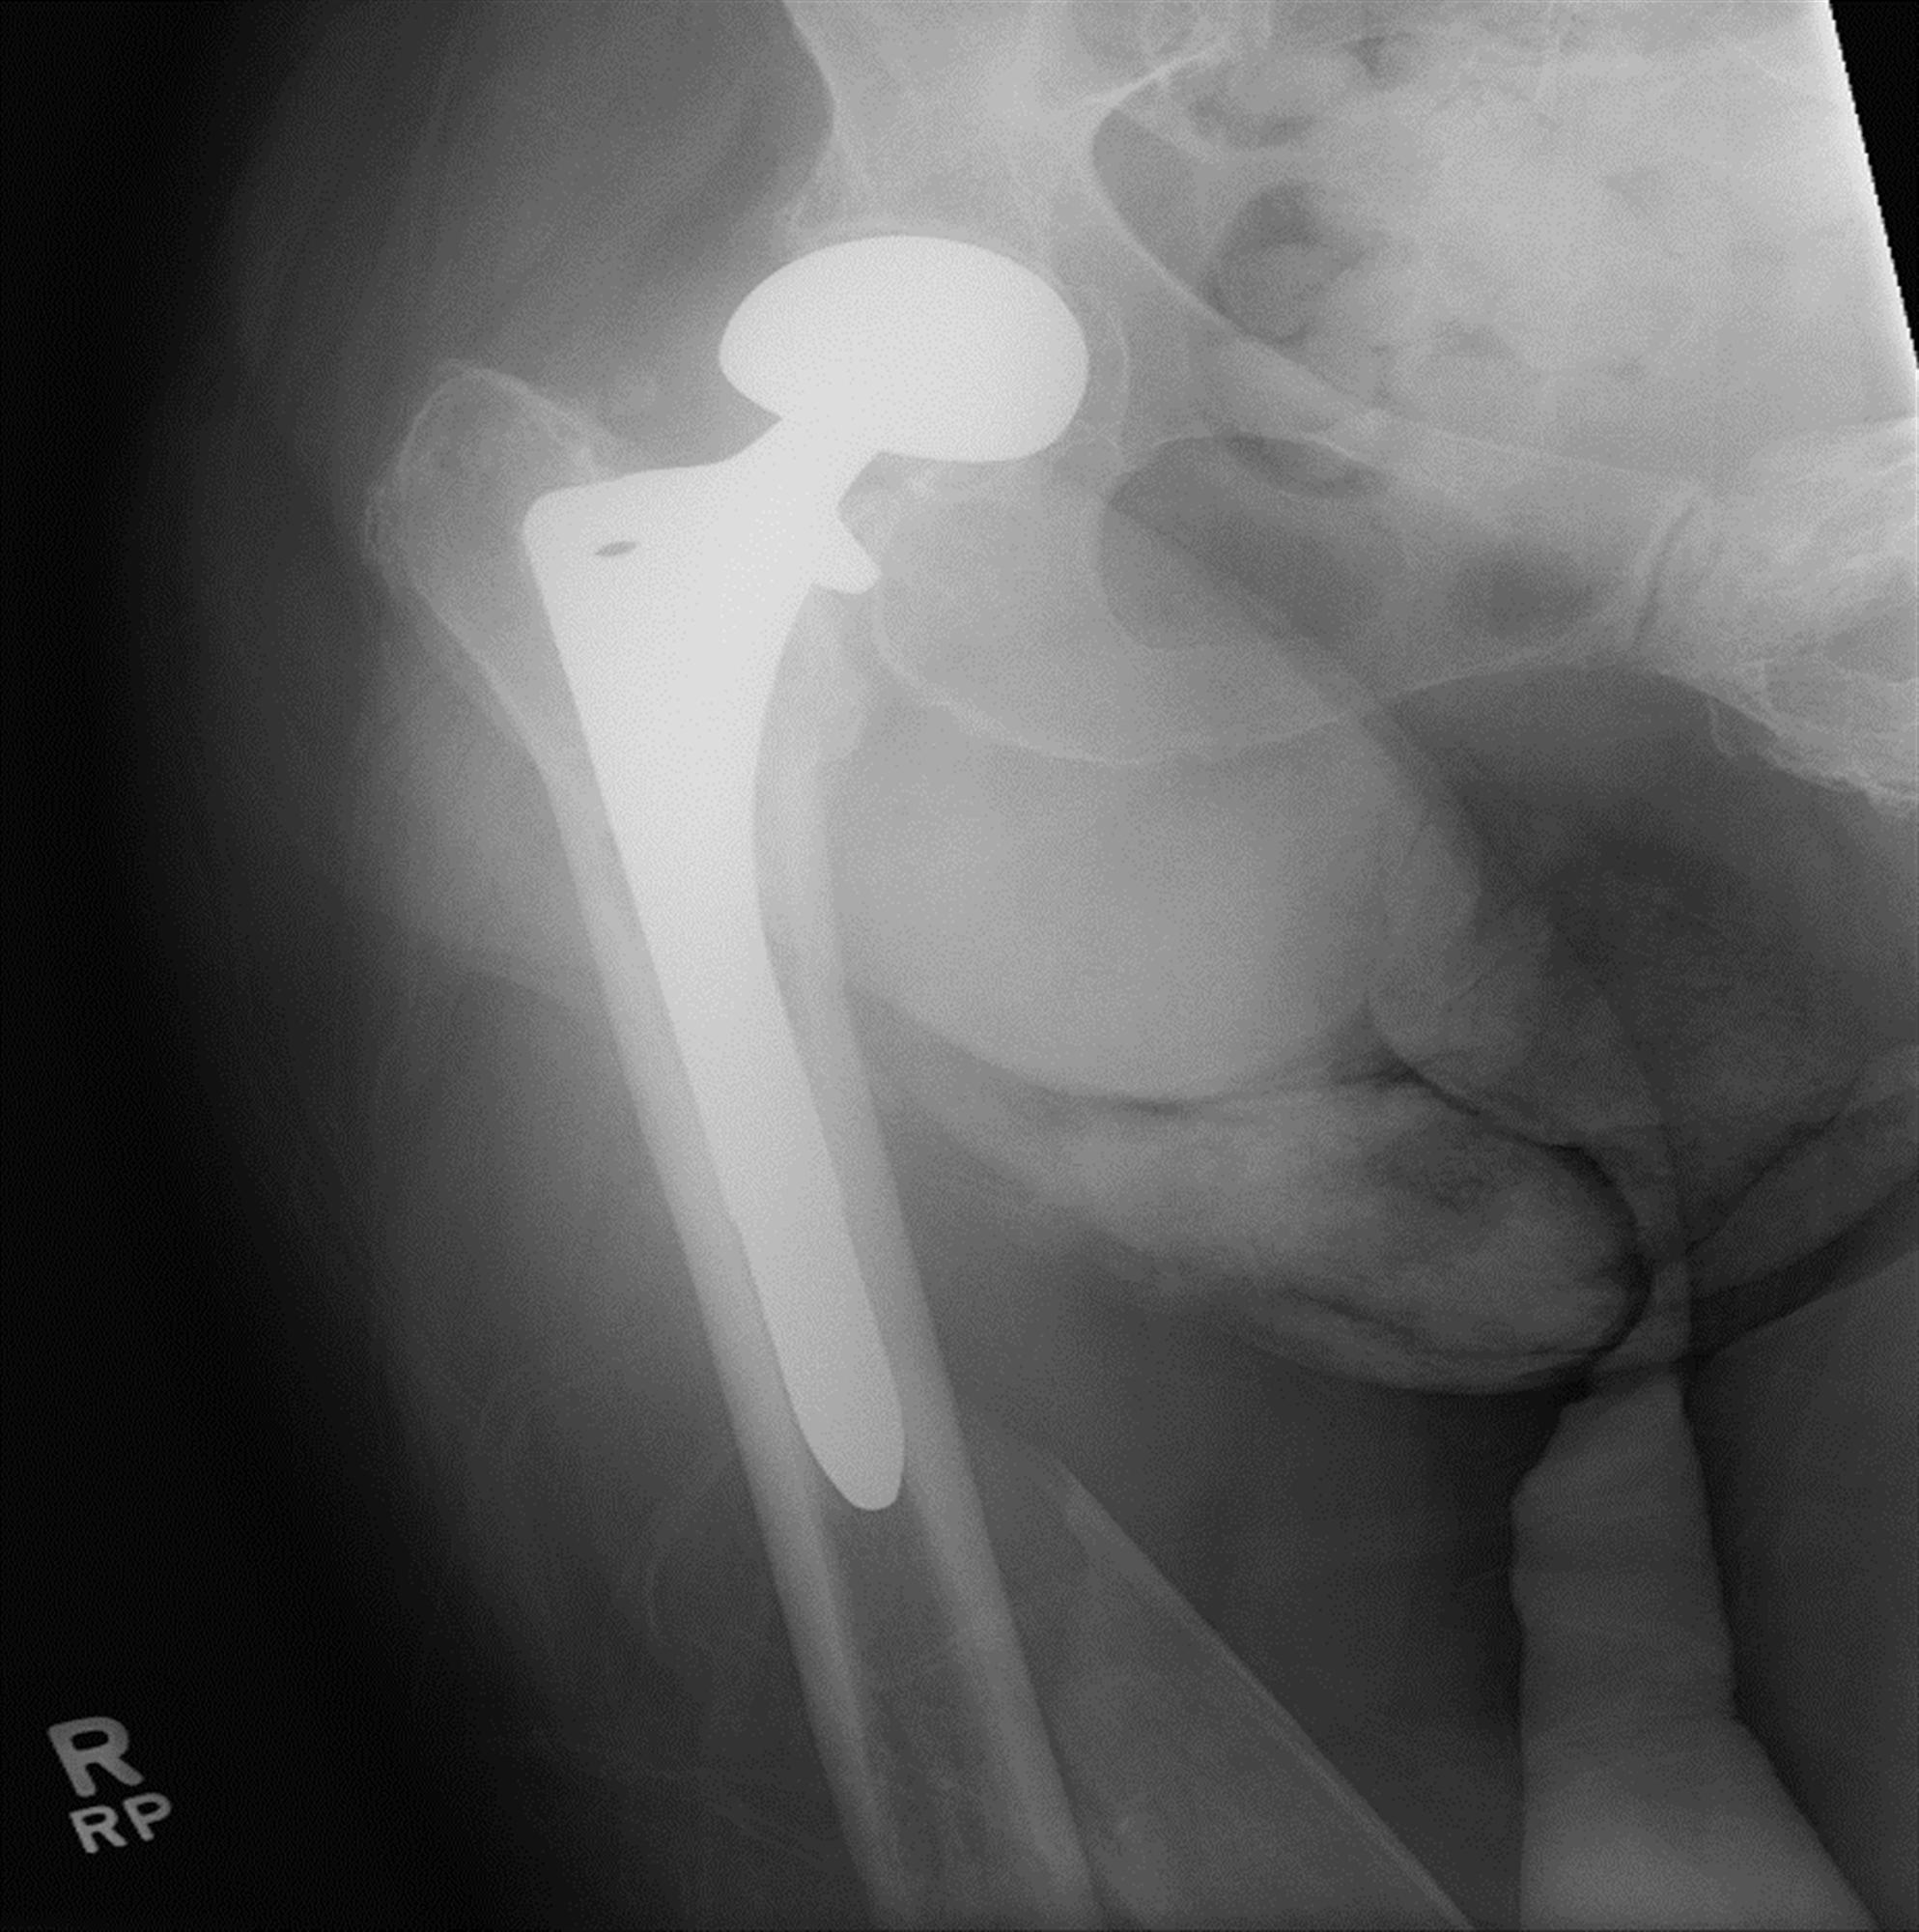

일상생활을 하다가 부러진 경우에도 똑같은 Vancouver Classification 을 사용합니다. 수술중과 큰 차이는 위치에 따라 골절을 나뉘고 B만 구체적으로 나누고 나머지는 그냥 A,C로 골절을 나뉩니다. STEM 이 헐거운 경우 B2, STEM 바로 아래는 B1, 삽입물 주변의 골절 또는 뼈가 부족한경우 B3로 이해하면 됩니다.